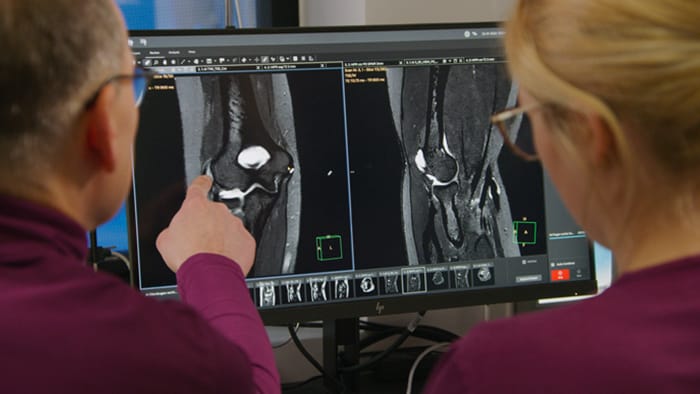

Previously, the practice wasn’t able to use 3D imaging on all joints, because the time required was too long, and on some joints it was simply not possible to achieve a good quality image, Dr. Schröter says. “Now, with SmartSpeed we consistently use 3D imaging for all joints and can thus discover the smallest changes, for example in the cartilage. And that, of course, helps us in making a detailed diagnosis.” Dr. Schröter says their MSK images show high contrast and extremely high quality. He mentions the menisci as an example. “We use a 3D proton density weighted fatsat sequence, thickness is 0.3 mm and scan time 3 minutes. The MPRs show an unbelievable resolution. Very small tears and even fraying of the tip of the meniscus become visible, which is normally only possible in arthroscopic surgery. When imaging the small joints of the fingers and the thumb we achieve extraordinary quality. Using SmartSpeed we succeed in displaying even very small structures anatomically correct, enabling us to see the extent of possible injuries. Tendons and ligaments appear with higher resolution so we can better see the injury pattern and describe and delimit it. Our referring physicians are fascinated by the extraordinary quality and high level of detail of the images. Patients are happy that the examination does not take too long. We hear from patients that it took a lot less time than they expected. This is especially important when scanning patients who are very uncomfortable in the MRI environment.”

SmartSpeed is used to reduce scan times. All three PDw orientations were obtained with only one 3D sequence using SmartSpeed. Performed with 1.5T Ambition X, 16ch dS Knee coil.